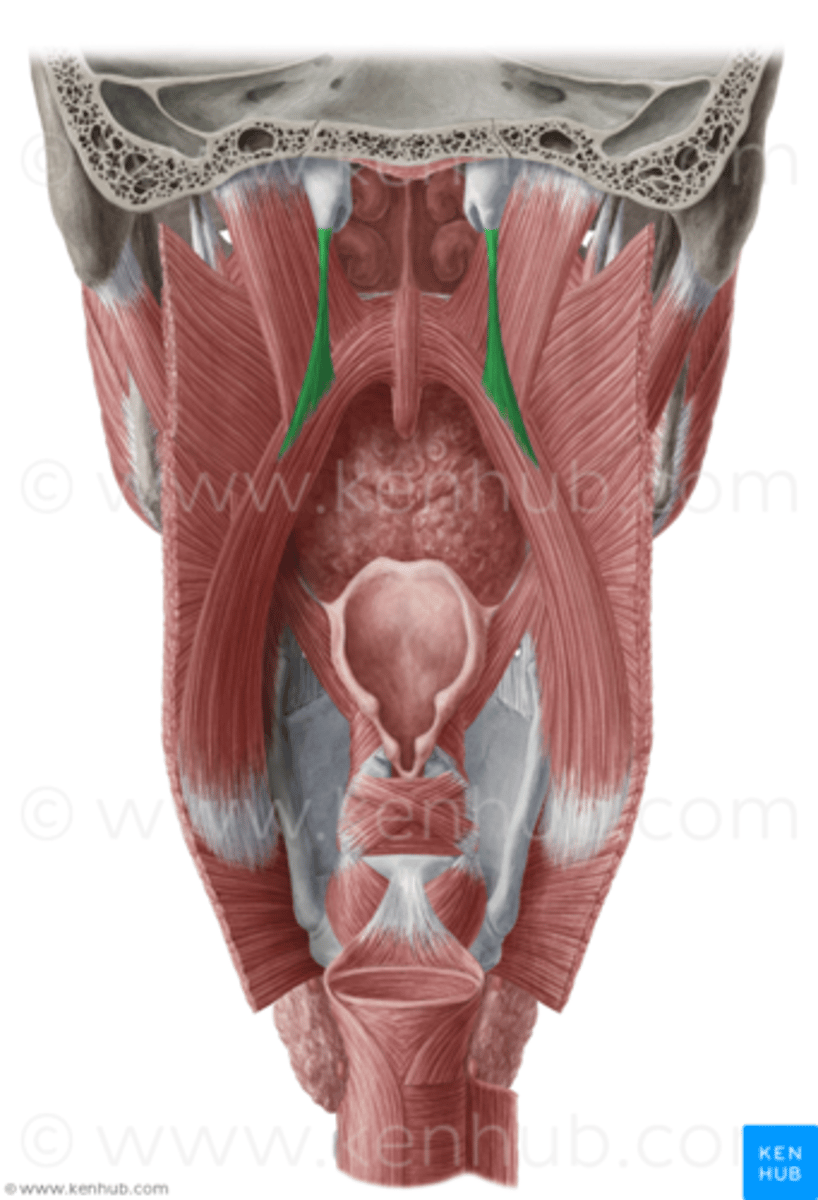

Salpingopharyngeus Figure

Salpingopharyngeus Description

Short thin muscle

Origin - lower border of the pharyngeal

orifice of the Eustachian tube

Course - inferior, deep to superior

constrictor

Insertion - blends with fibers of palatopharyngeus muscle

Action - elevate and dilate pharynx